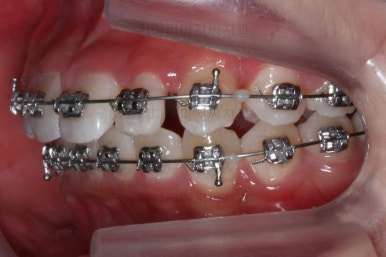

이번에 사용한 장치는 메탈장치였고, 치료 초기에는 매복치를 제대로 꺼내는데 초점을 맞췄어요.

장치를 부착하고 철사를 조절해주면 서서히 나옵니다.

처음 장치를 부착한 이 후 8개월이 흐른 시점이네요. 꽤나 오랫동안 천천히 송곳니를 가지런하게 해줘요.

치료 10개월째의 모습입니다.

이정도면 다 끝난 것 같은 느낌이 드시지 않나요? 과개교합도 개선시켰고 매복치아 덧니도 가지런하게 했어요.